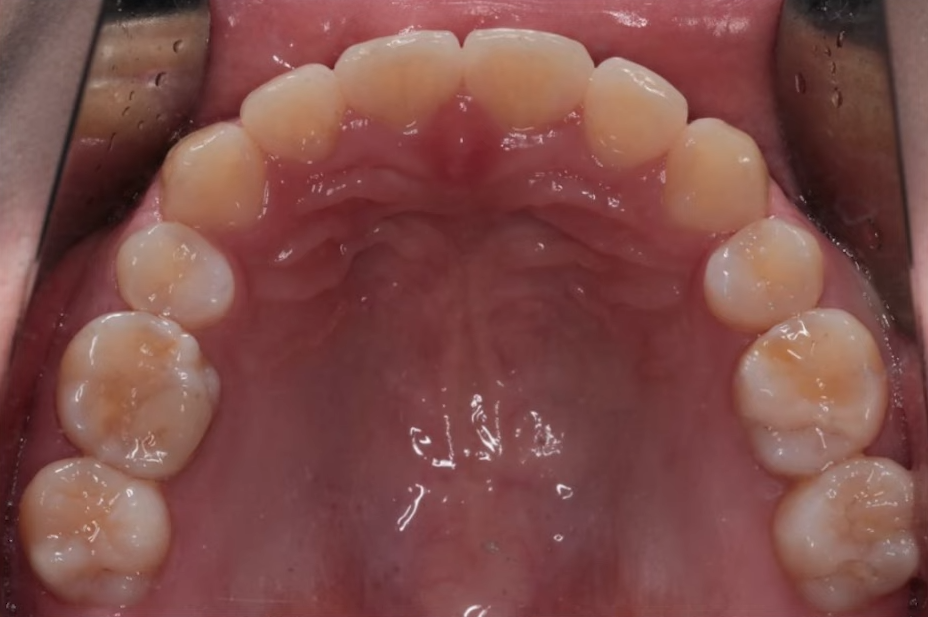

뻐드러져 있던 치아 배열 모습이 정상적으로 돌아온 걸 확인하실 수 있을 겁니다.

기울어졌던 앞니가 정상 각도로 줄어들었고 자연스레 돌출입도 개선된 걸 볼 수 있지요.

입술 라인도 부드럽고 자연스럽게 닫히며,

잇몸 노출도 줄어들어 웃는 인상까지 부드러워졌는데요.

교정 끝난 뒤엔 라미네이트도 추가해 앞니 라인이나 색상까지 정리해 드렸습니다.